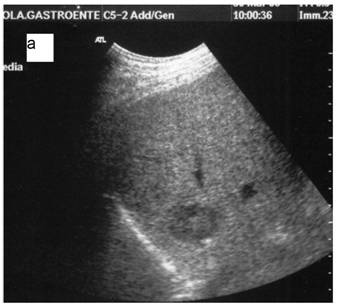

Fig 5

a: Ipoechoic nodule of the VII liver segment in a non cirrhotic liver pattern, normal hepatic vein. b: The same nodule after RF session.